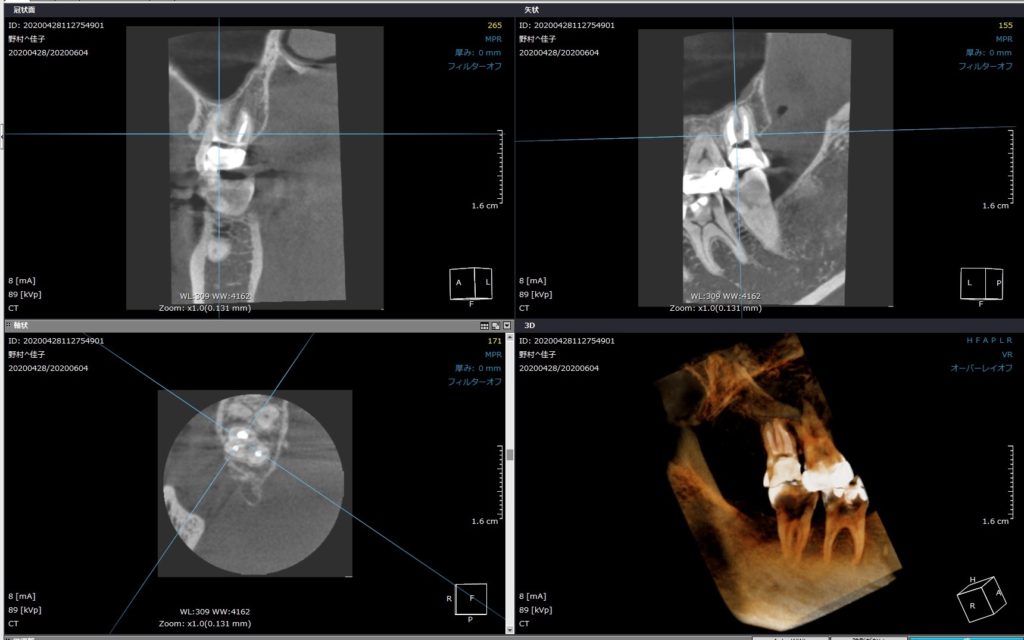

根管治療が完了しました。その後のCT撮影での確認です。